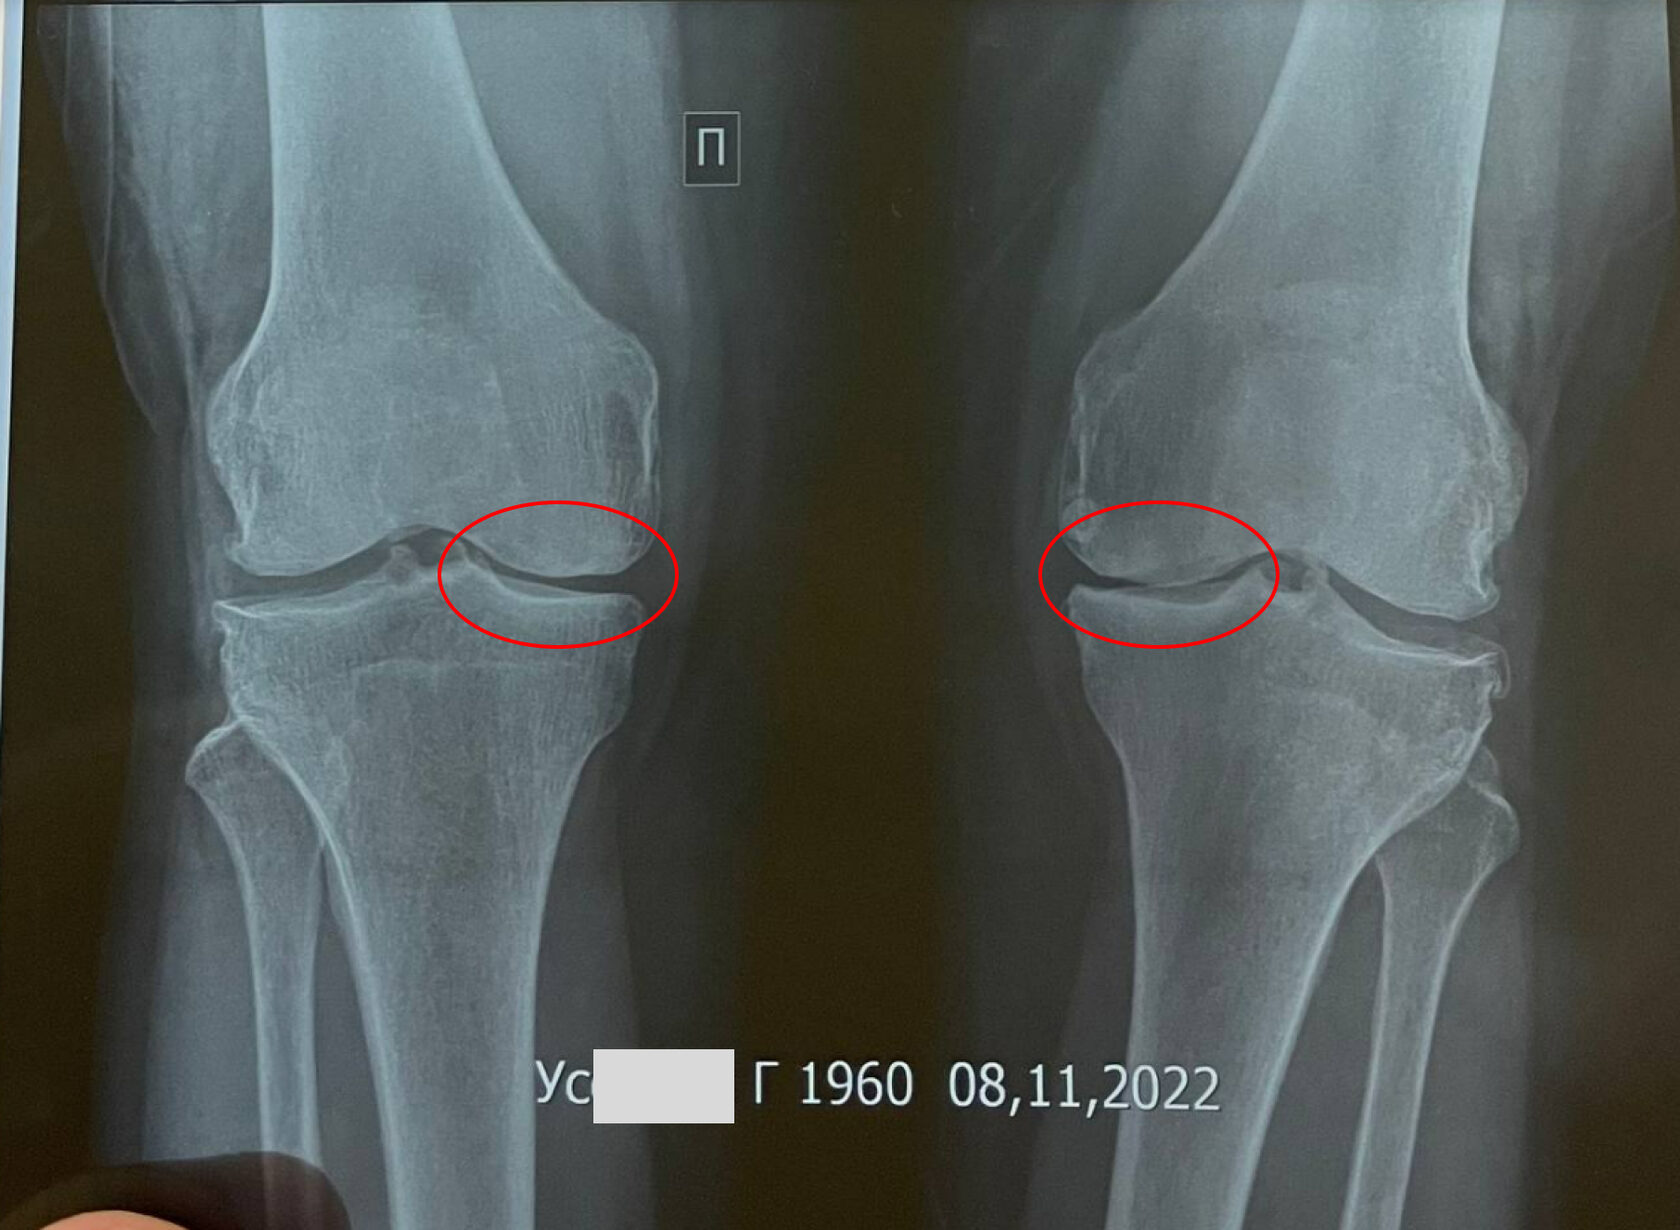

Со слов пациентки боли беспокоят в течение 5 лет. За последние месяцы боли усилились. Ни с чем не связывает. Получала лечение у ревмотолога. В данное время принимает обезболивающие. Временный эффект. На рентген снимке: Признаки Гонартроза 3-4 степени. Сужение в медиальной части. На рентгене после положительная динамика за 1 курс в виде уменьшения степени артроза, увеличения суставной щели особенно в медиальной части. Продолжает лечение в Inject Clinic.

Заключение:

Признаки Гонартроза 3-4 степени. Сужение в медиальной части. Остеофиты.

ОБСЛЕДОВАНИЯ НА МОМЕНТ НАЧАЛА ЛЕЧЕНИЯ

Жалобы: боли в коленных суставах, больше справа, режущего характера, при движении усиливается, при спуске с лестницы чувствуется тяжесть, при вставании с места ощущает щелчок, отек, боли в спине ноющего характера. Болевой синдром по шкале оценки боли 8 из 10

Жалобы: Жалобы на редкие боли в коленных суставах, больше слева. Болевой синдром в коленном суставе по шкале оценки боли 2 из 10

Признаки гоноартроза 2-3 степени. Остеофиты

ОБСЛЕДОВАНИЯ ПОСЛЕ ЛЕЧЕНИЯ

Диагноз: Гонартроз коленных суставов, 3 ст. Синовит

Возраст пациента: 62 года

Пол: женский

РЕЗУЛЬТАТ ЛЕЧЕНИЯ